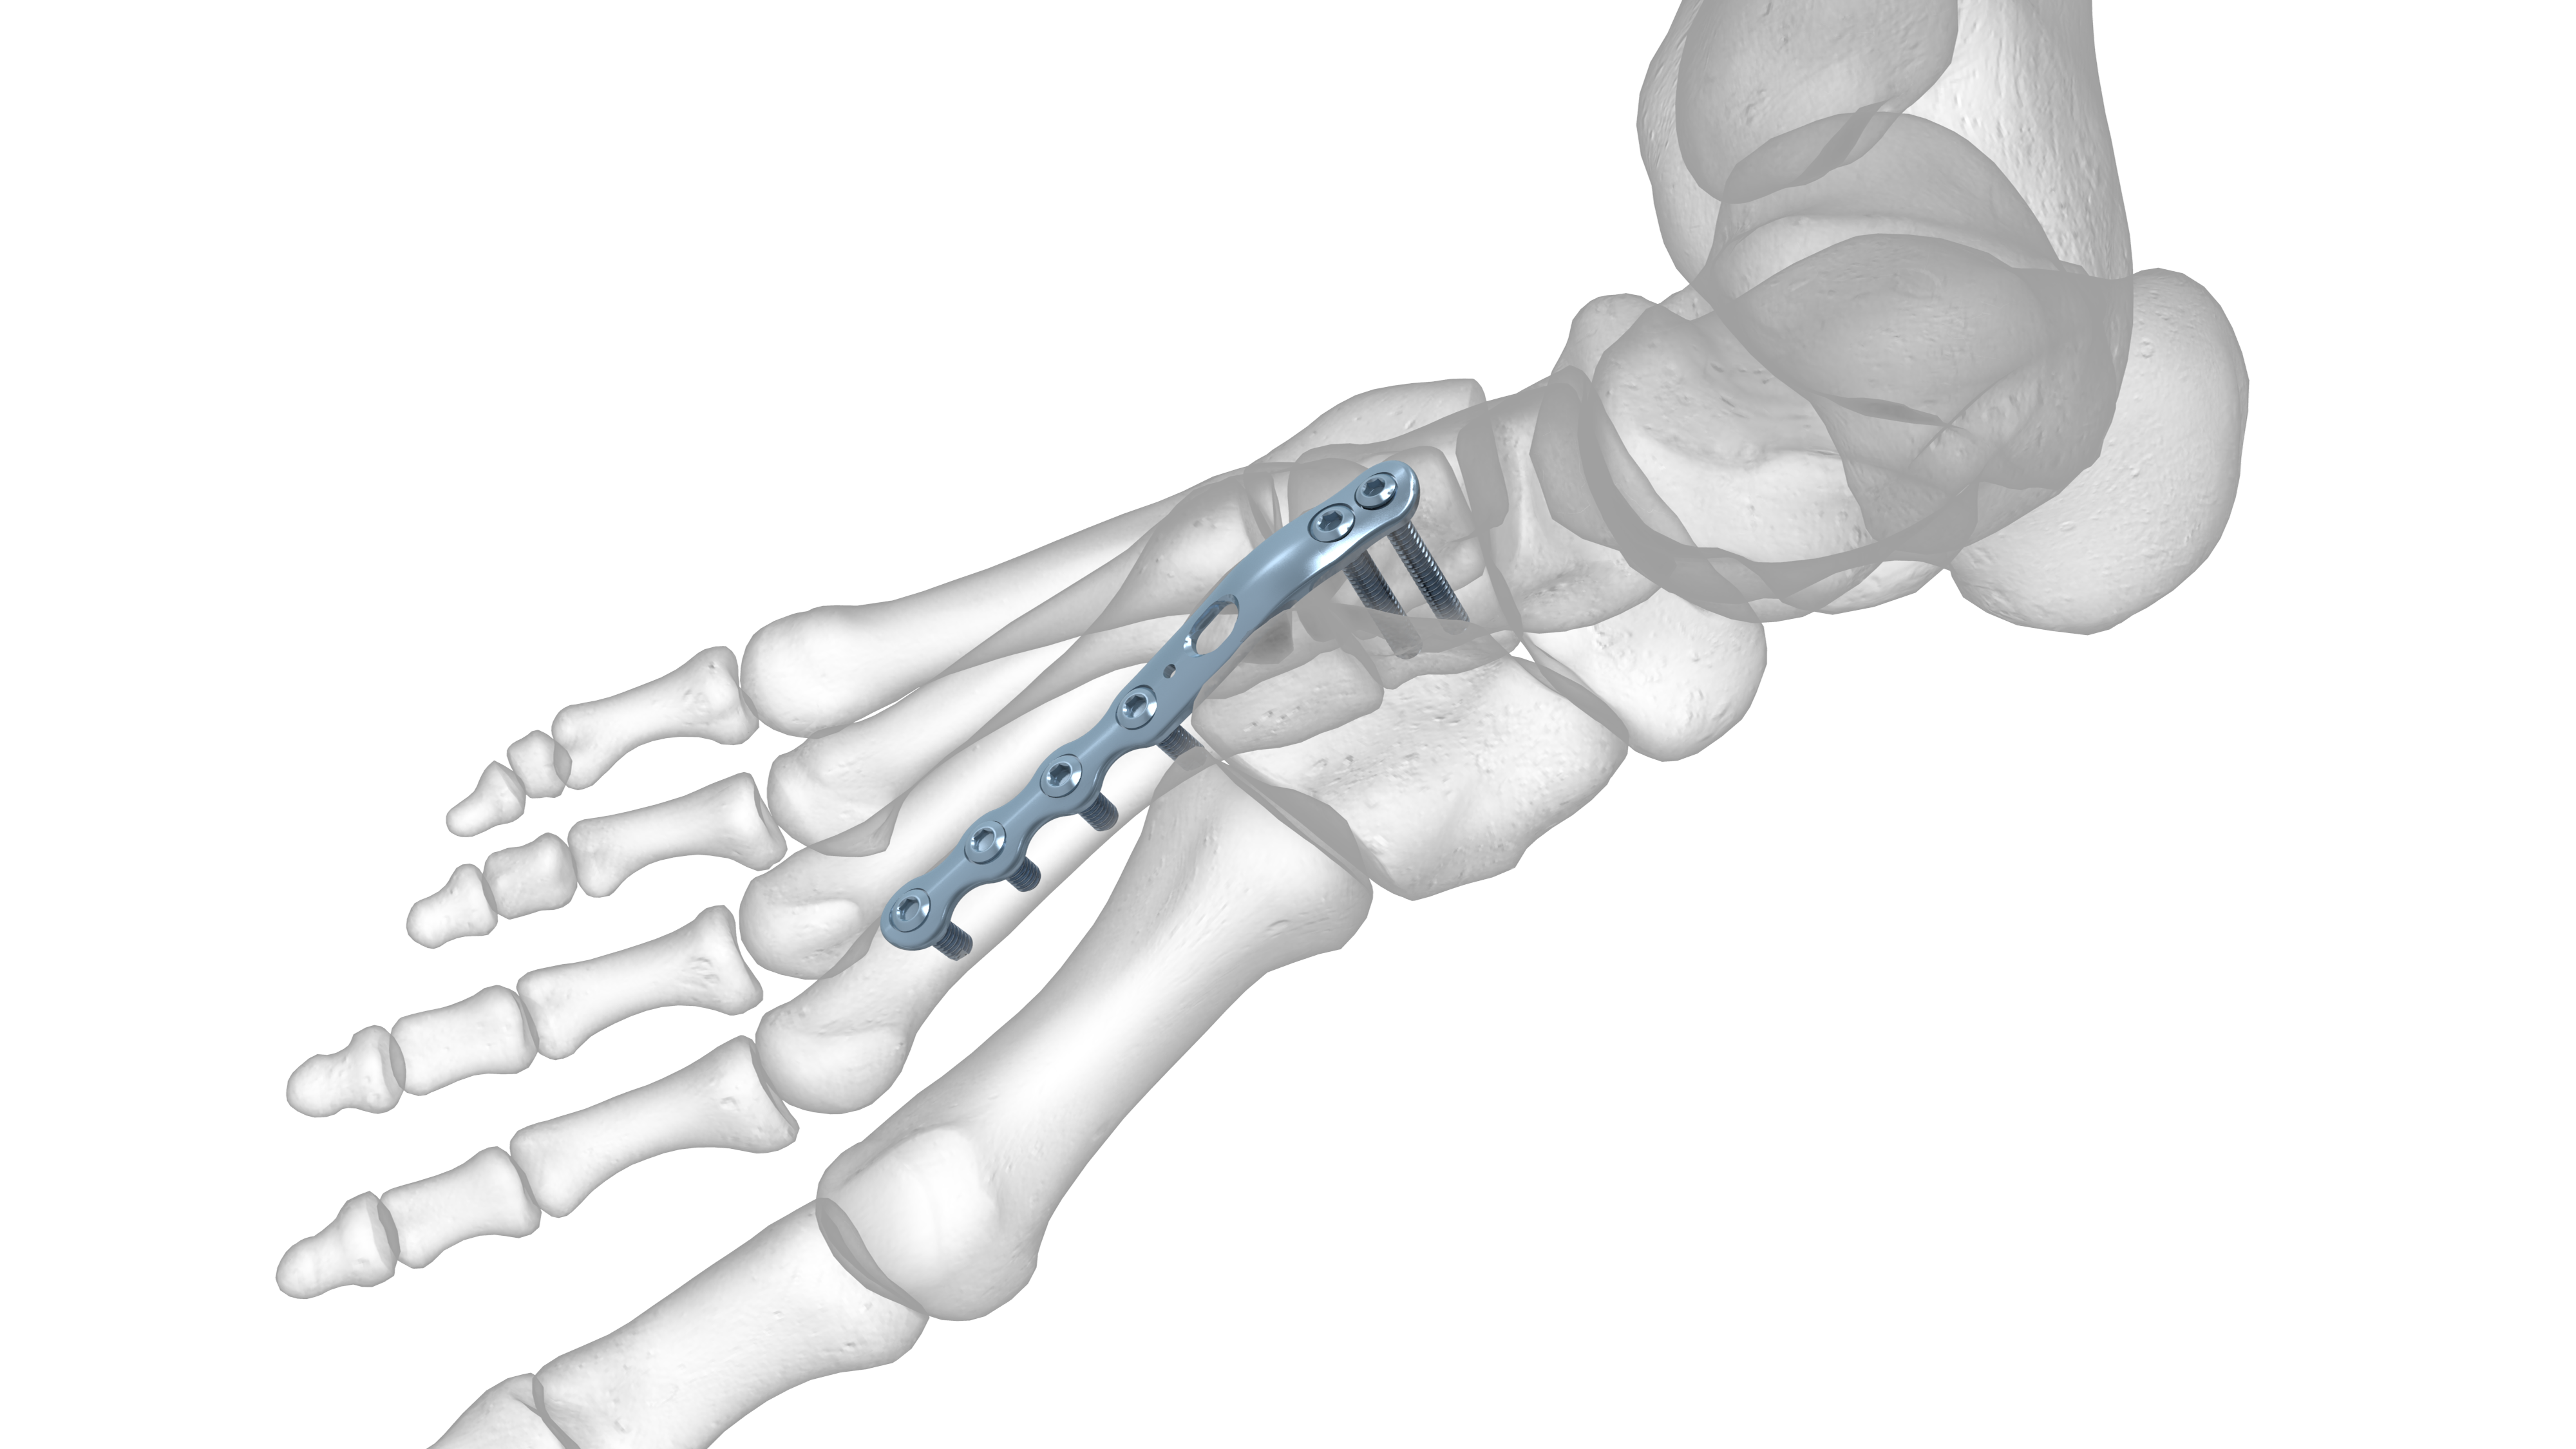

From www.acumed.net

Extended 2nd and 3rd Ray TMT Plate Acumed What Are Tmt Joints Articulationes tarsometatarsales) are three synovial plane type joints located in the foot. The tarsometatarsal joints (lisfranc's) are arthrodial joints. Some authors combine the medial and middle columns into the medial column as the three tarsometatarsal (tmt) joints are relatively immobile. The bones entering into their formation are the first, second, and third cuneiforms, and the cuboid, which articulate with. Midfoot. What Are Tmt Joints.